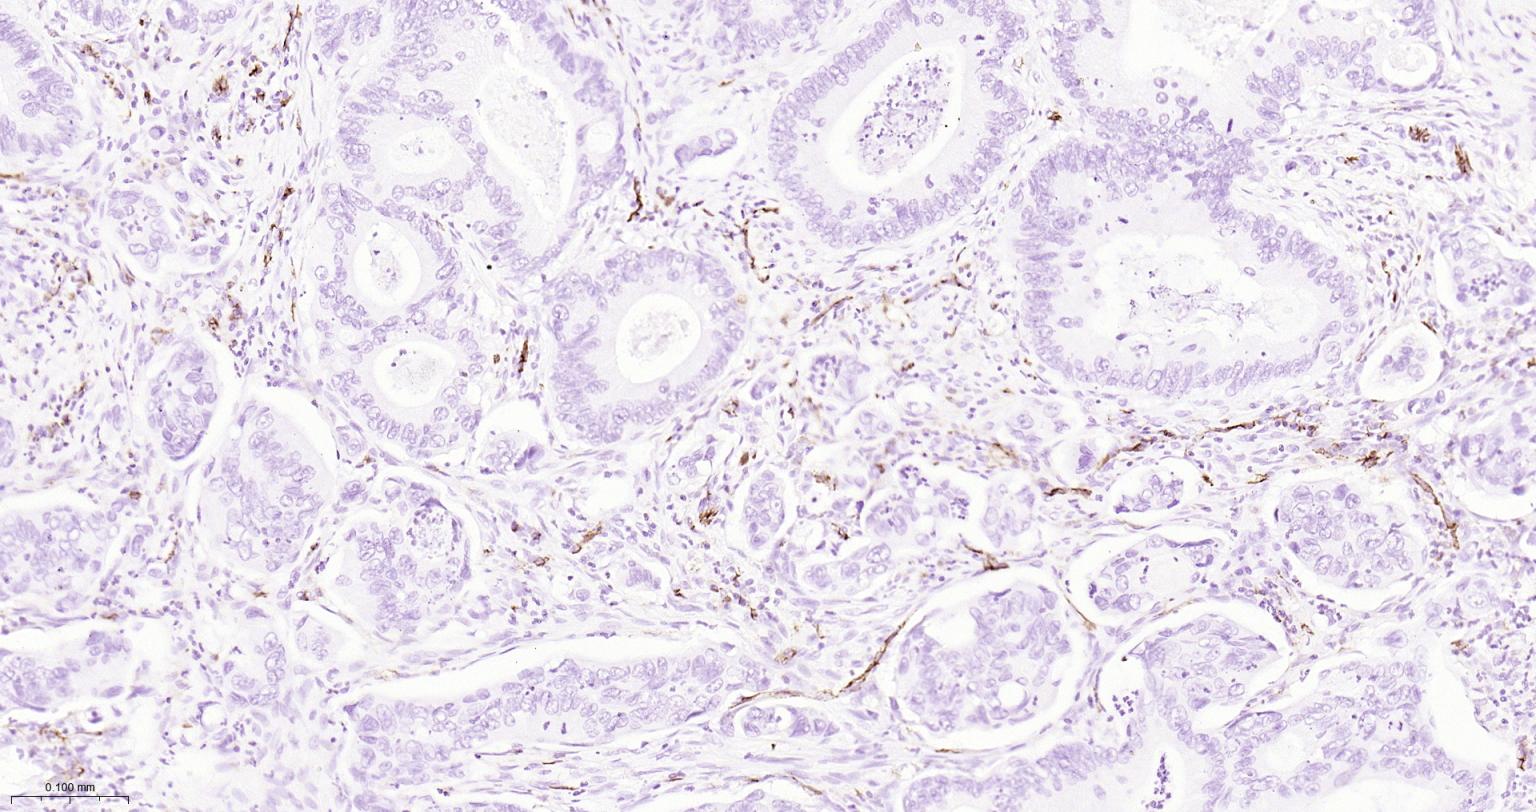

| IHC-P | Human | 1:200-2000 | |

Expressed on platelets and leukocytes and is primarily concentrated at the borders between endothelial cells (PubMed:18388311, PubMed:21464369).

Cell adhesion molecule which is required for leukocyte transendothelial migration (TEM) under most inflammatory conditions (PubMed:19342684, PubMed:17580308).